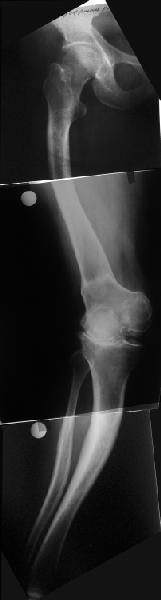

Обратилась дама 57 лет с намерением протезировать коленный сустав. Имется грубая осевая деформация (см. рентгенограммы). Встает вопрос насчет улучшения оси конечности. Даже с мобилизацией на пртяжении при таком вальгусе малоберцовому нерву может не поздоровиться. Уважаемые коллеги, как лучше провести коррекцию? Какой сегмент, на каком уровне, на какую величину? Что бы Вы исправили до протезирования, что можно оставить и сделать вместе с замещением сустава?

В данном случае перед эндопротезированием мы бы корригировали оси бедренной и большеберцовой костей (см. вложение). Дистальный эпидиафизарный угол бедра будет корригирован при эндопротезировании. Тип остеотомии и коррекции деформации (клиновидная резекция - одномоментная коррекция; формироване треугольных или трапециевидных регенератов во времени) - исходя из

относительной длины конечности.

На бедре дистальный отдел в сгибательной установке после, видимо, когда-то сделанной корригирующей остеотомии. Не надо ли на том же уровне все-таки "разогнуть" бедро до протезирования? Сам протез, наверно, можно поставить в большем или меньшем "сгибании", но весь дистальный эпиметафиз бедра и все нижележащее оказывается кзади от механической оси бедра. Насколько это допустимо, не ведет ли к расшатыванию протеза? Или можно как-то рассчитать такой наклон протеза, что он компенсирует это смещение?

И нет ли смысла аппаратом исправить не только кривые диафизы, но и взимоотношения собственно суставных концов бедренной и большеберцовой костей, они ведь там контактируют с вальгусом градусов 25? Это позволит дозированно удлинить мягкие ткани по латеральной стороне.

Это один из самых сложных вариантов для эндопротезирования, т.к. мы имеем деформацию бедренной кости в трех проекция, думаю, что есть и

ротационная деформация, плюс к этому - деформация голени. Однозначно в таких случаях, в отличии от возможностей при эндопротезировании ТБС необходимо выполнить корригирующие остетомии на двух уровнях. Что касается сгибательно установки мыщелков бедра - думаю, что это не является проблемой, особенно если на операции будет испрользован заднестабилизированный протез. Относительно вальгуса - все не так однозначно - возможно, что деформация слегка преувеличена за счет проекционной установки из-за ротационной деформации. Поэтому планирование операции необходимо будет делать только после коррекции деформации.